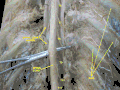

Médula espinal. Membranas y las raíces nerviosas espinales. Disección profunda. Vista posterior.